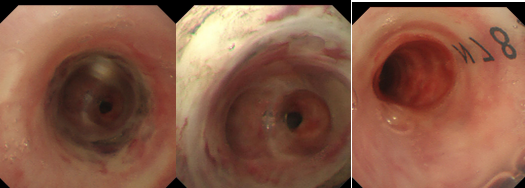

气管下段狭窄激光治疗+Y型硅酮支架植入后

术后患者呼吸困难等症状得到了立竿见影的缓解,术后第二天复查支气管镜可见支架在位良好,管腔通畅。大大改善了患者的生活质量,患者于术后第三天下午顺利出院。